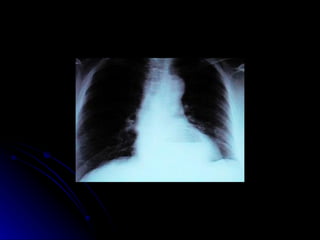

SISTEMA DIGESTÓRIO Esôfago Tubo muscular envolvido na deglutição, responsável por levar o alimento da orofaringe até o estômago 23 a 25 cm de comprimento Dividido em partes cervical, torácica e abdominal

SISTEMA DIGESTÓRIO Esôfago Inicia-se na altura da cartilagem cricóide, na projeção da 6ª VC, com trajeto descendente à frente da coluna vertebral, atravessa o mediastino superior e posterior e penetra no abdome através do hiato esofágico ao nível da 10ª VT e termina no cárdia ao nível da 11ª VT.

SISTEMA DIGESTÓRIO Possui 2 curvaturas laterais para a esquerda e 2 curvaturas no plano antero-posterior , acompanhando a coluna vertebral Possui 4 constricções EES- 15 cm Arco da Aorta- 22,5 Brônquio esquerdo- 27,5 Diafragma- 40 cm

SISTEMA DIGESTÓRIO Esôfago cervical Íntima relação com a traquéia Esfíncter esofagiano superior Relações anatômicas Traquéia, carótidas, tireóide, coluna vertebral Irrigação Ramos da tireóidea inferior Inervação Nervo vago e tronco simpático Linfáticos

SISTEMA DIGESTÓRIO Esôfago torácico Relações anatômicas Anterior- traquéia,brônquio esquerdo, vasos pulmonares, pericárdio e diafragma Posterior- coluna vertebral, aa. Intercostais direita, ducto torácico e vv. hemiázigos

SISTEMA DIGESTÓRIO Esôfago torácico Relações anatômicas Esquerda- arco aórtico,aa. subclávia esquerda, ducto torácico, nervo recorrente esquerdo, pleura esquerda e aorta descendente torácica e nervo vago esquerdo Direita- pleura direita, vv. Ázigos e nervo vago direito Irrigação  Ramos da aorta descendente Artérias bronquiais Inervação  Nervo vago e tronco simpático